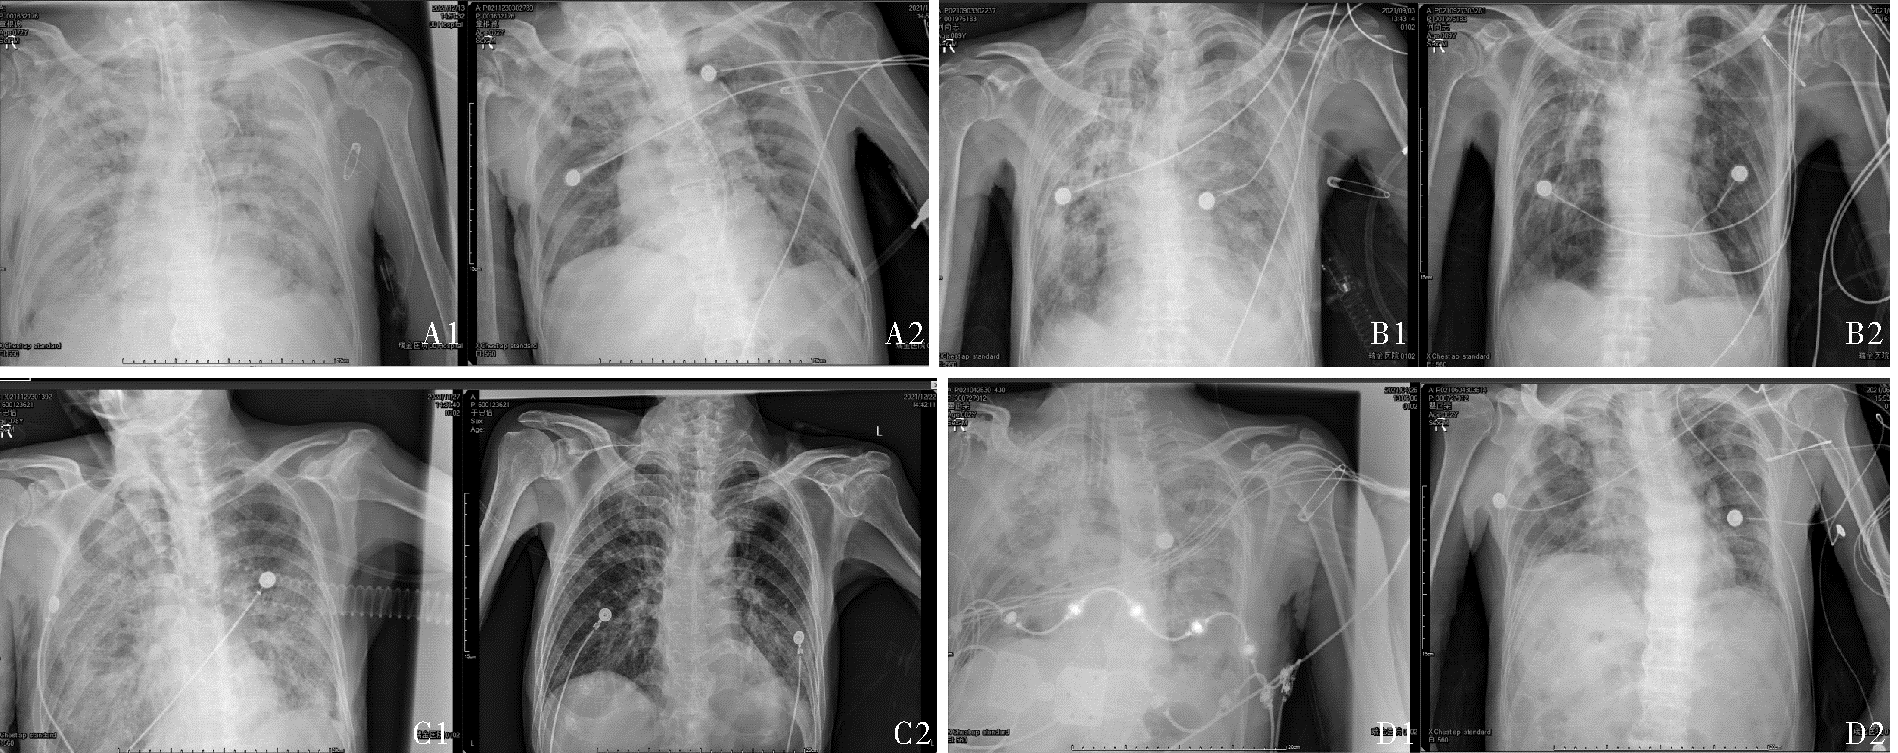

目的:探讨免疫功能正常的重症Ⅰ型单纯疱疹病毒(type Ⅰ herpes simplex virus,HSV-1)肺炎的诊治思路。方法:收集和回顾4例2021年4月至12月入住开云网页登录 医学院附属瑞金医院呼吸重症监护室(respiratory intensive care unit,RICU)诊断为重症HSV-1肺炎患者的诊治过程,并复习国内外相关文献。4例患者均为男性,年龄72~89岁。结果:4例患者以发热、咳嗽、咳痰(部分患者有血性痰)、气喘和呼吸困难为主要症状。患者均出现重度Ⅰ型呼吸衰竭,感染指标均上升,同时淋巴细胞计数相对下降,CD3、CD4、CD8绝对计数在治疗后均出现明显上升。呼吸道标本的宏基因组二代测序(metagenomic next generation sequencing, mNGS)中都检测到HSV-1。所有患者采用早期抗病毒、激素抗炎,呼吸支持治疗后,病情均好转,其中3例治愈出院。文献共检索到免疫力低下的HSV-1肺炎26例,免疫功能正常3例。29例患者的临床症状、体征缺乏特异性,经验性给予抗细菌或真菌治疗无效后,多数进一步完善肺泡灌洗液病原学检查,证实HSV-1感染后,积极给予阿昔洛韦抗病毒治疗,部分患者联合激素治疗,3例免疫功能正常者病情均好转,26例免疫力低下者中22例好转,4例死亡。结论高龄重症HSV-1性肺炎临床表现缺乏特异性,诊断存在一定难度。呼吸道分泌物mNGS检查联合常规实验室检查有助于该病的诊断。早期认识该病,予以抗病毒药物,短程使用糖皮质激素治疗可有效治疗该病。

| 病例 | 呼吸支持方式 | 俯卧位 | 抗病毒 | 激素(甲泼尼龙) | 增强免疫力 | 预后 | |||||

|---|---|---|---|---|---|---|---|---|---|---|---|

| 药物及剂量 | 疗程(d) | 是否使用 | 剂量及疗程 | 免疫球蛋白 | 胸腺肽类 | ||||||

| 1 | IMV | - | 阿昔洛韦 0.4 g 鼻饲tid |

14 | + | 40 mg ×10 d | + | - | 好转 | ||

| 2 | HFNC/NIV交替 | - | 伐昔洛韦 0.3 g鼻饲 bid |

7 | - | - | - | + | 痊愈出院 | ||

| 3 | HFNC | - | 阿昔洛韦 0.4 g口服 tid |

14 | + | 40 mg ×9 d | - | - | 痊愈出院 | ||

| 4 | IMV | + | 伐昔洛韦 0.3 g鼻饲q12 h |

45 | + | 120 mg ×3 d 80 mg ×14 d |

+ | - | 痊愈出院 | ||